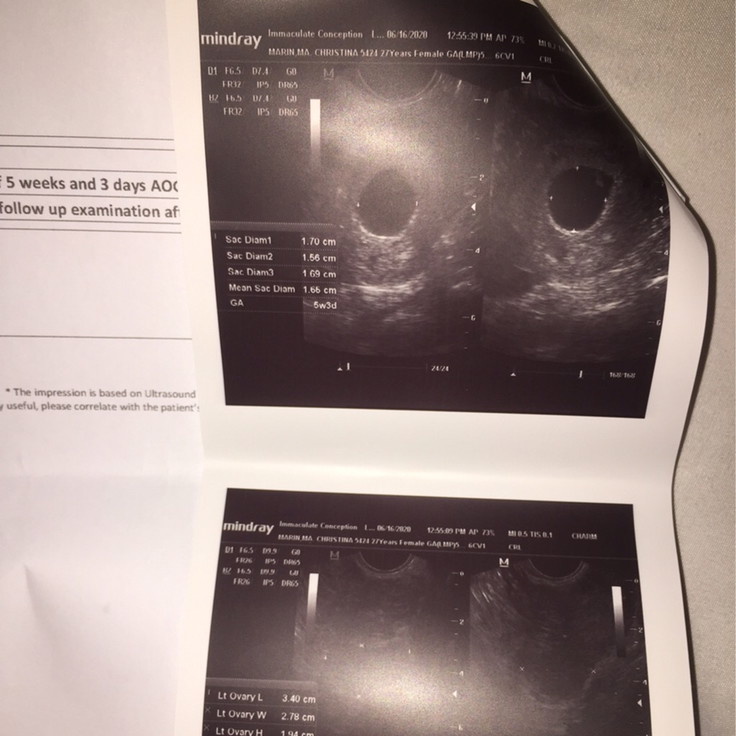

mommies, need your advice esp sa nakaranas na rin ng ganito. first day of lmp ko ay apr 28 so 6 wks pregnant na dapat ako. first check up and ultrasound ko ngayon pero wala pang baby :( may gestasional sac and yolk sac pero wala pang embryo. kung 5wks normal daw ito pero sa last mens ko 6 weeks na dapat ako. repeat transv ako after 2 weeks. nagwoworry ako nakunan kasi ako 3 yrs ago at ngaun lng ako nabuntis uli at gustong gusto ko na magkababy :( meron naba nakaranas sainyo ng ganito and turned out na normal and healthy naman si baby? na baka nalate lng sya ng pakita sa ultrasound? parang ang tagal tuloy ng 2 weeks na paghhintay ko ayaw ko mastress pero di ko maiwasan magworry :(